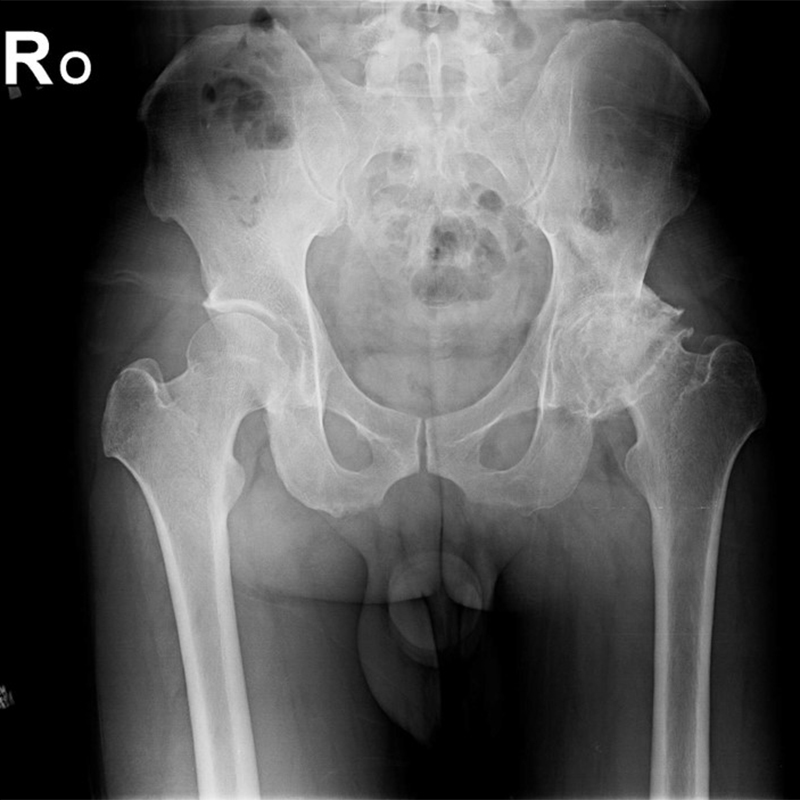

傳統髖關節置換 首頁 案例分享 髖關節手術 傳統髖關節置換 54歲蔡先生退化性關節炎 術前 術後 張女士 51歲 退化性關節炎(DDH先天發育不全 CROWE TYPE 2) 術前 術後 38歲林先生 退化性關節炎 術前 術後 72歲謝女士 退化性關節炎 術前 術後 71歲 謬女士 骨股頭壞死 術前 術後 50歲 郭先生骨股頭壞死 術前 術後 80歲 盧先生骨股頭壞死 術前 術後 林先生 37歲 術前 術後 邱女士 51歲 術前 術後 張女士 50歲 術前 術後